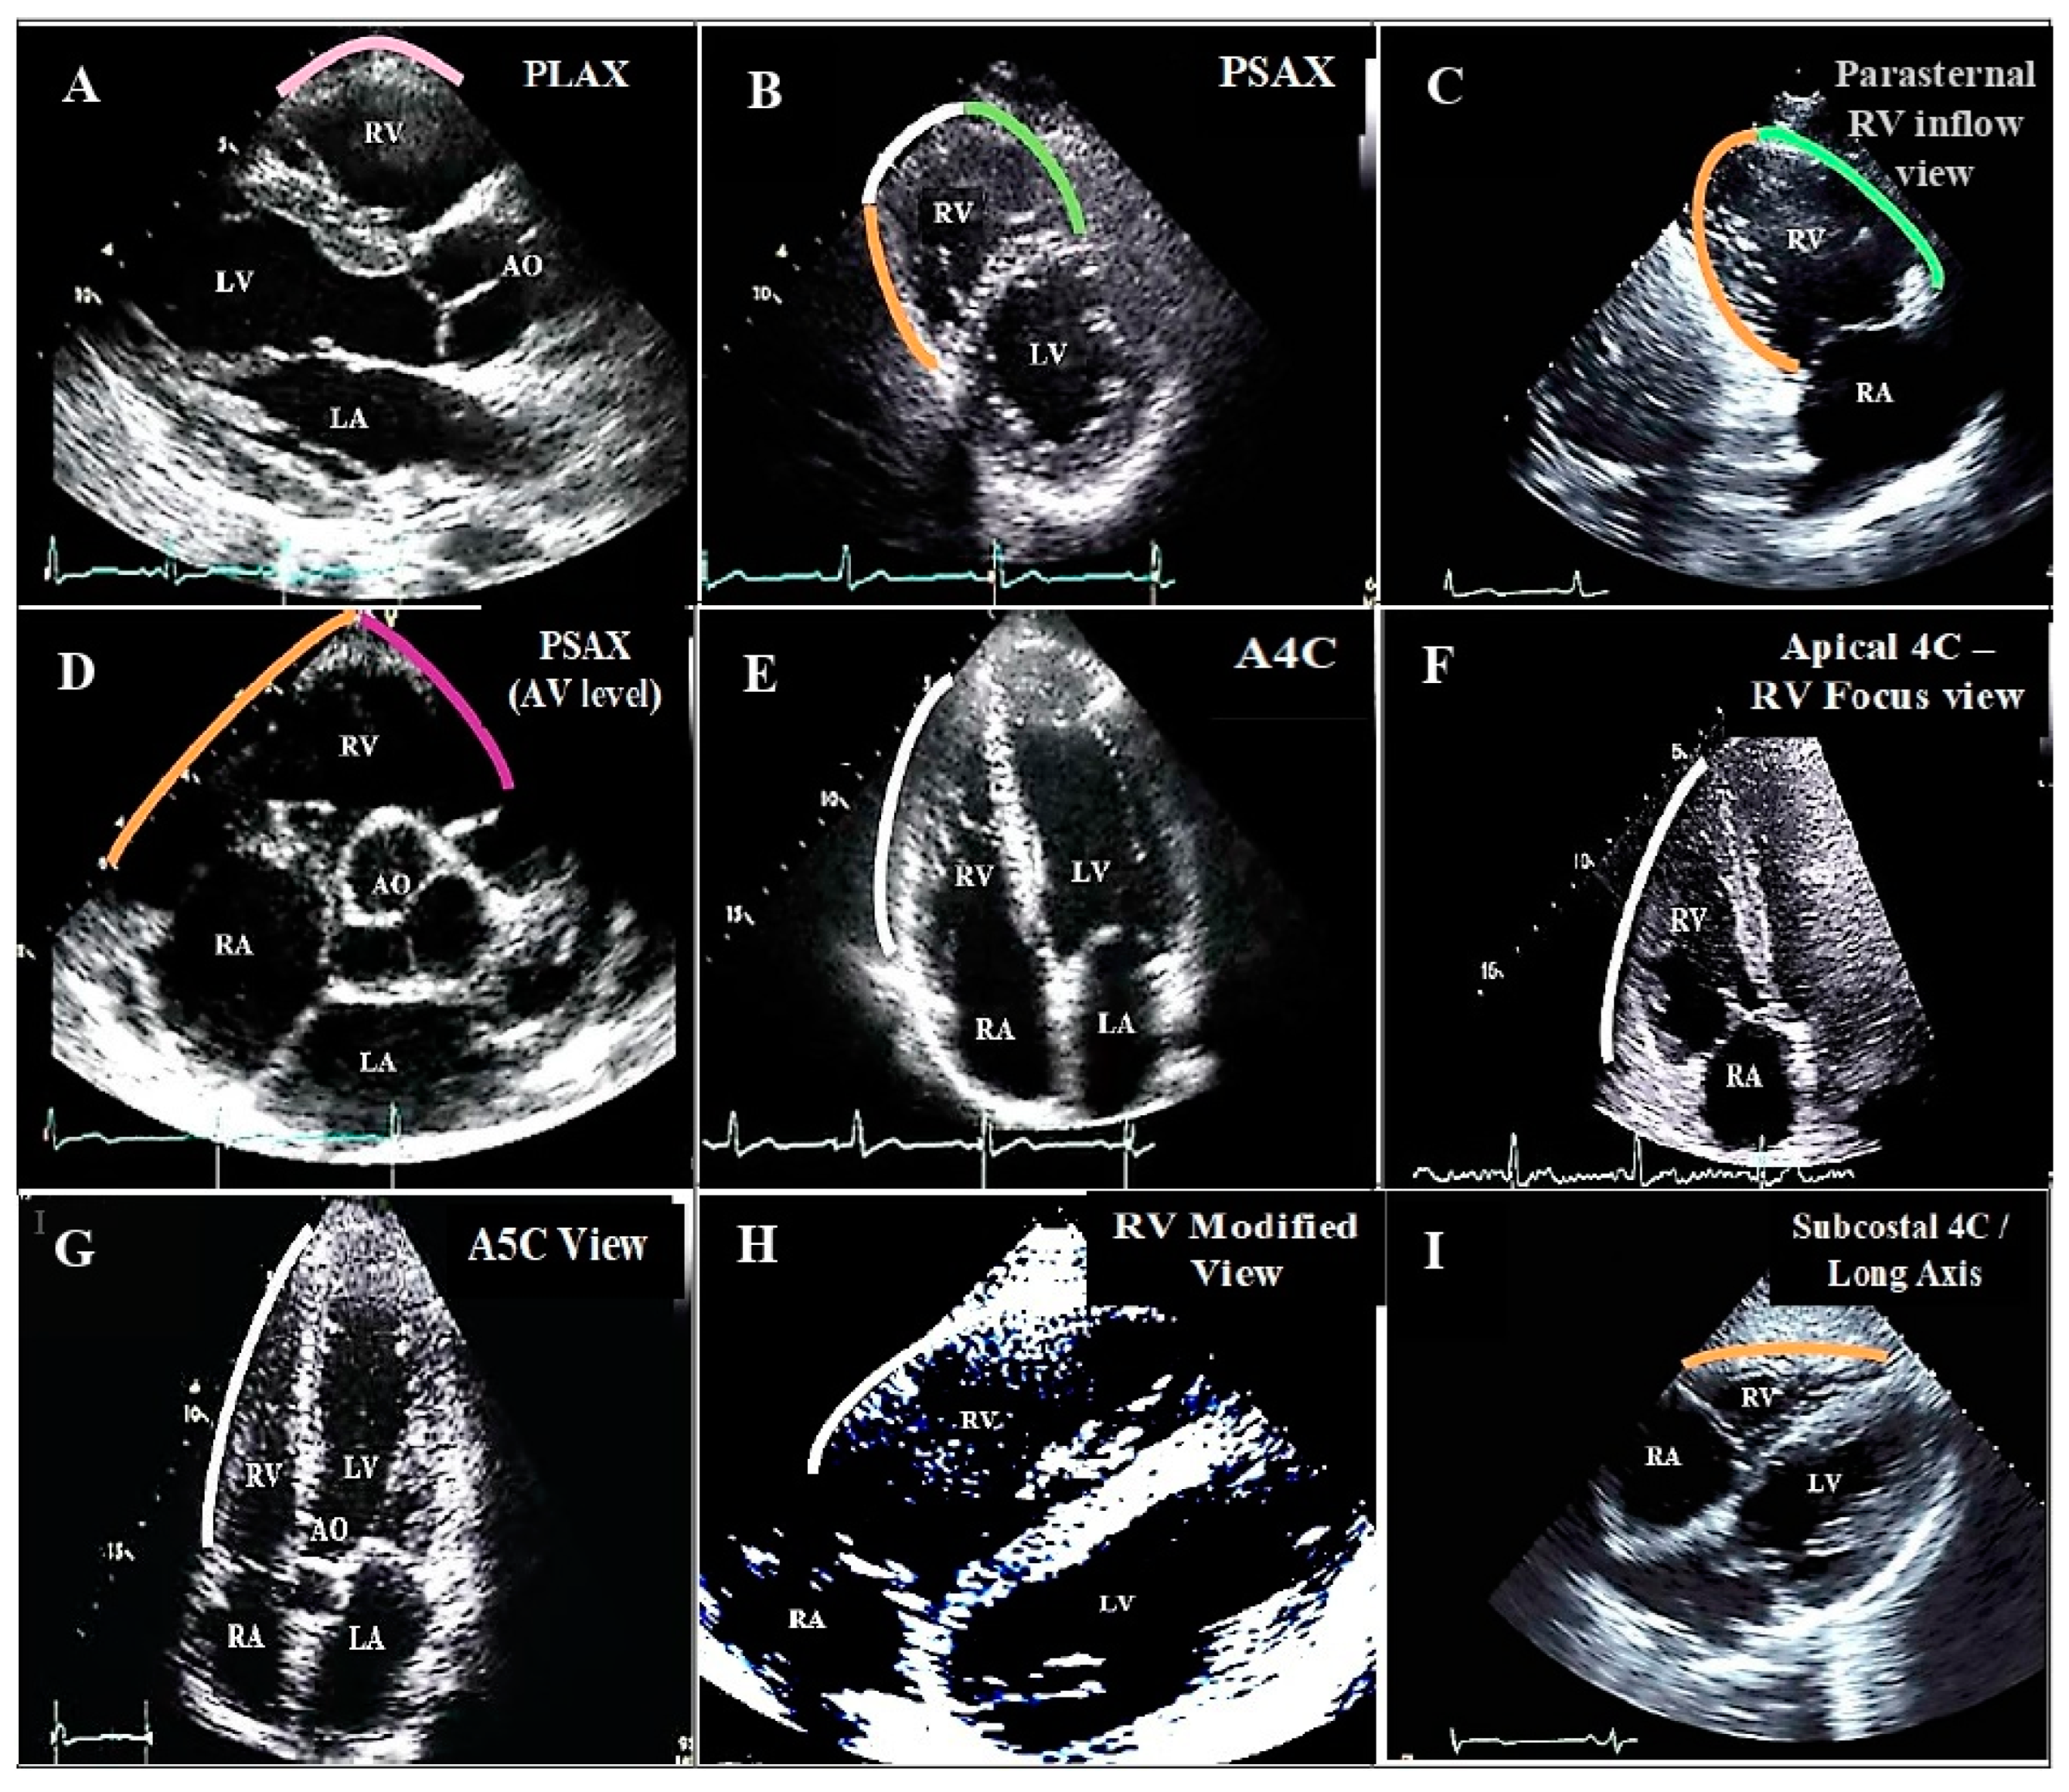

Inferior wall of the RV: supplied by the posterior descending artery. Abbreviations: A5C: apical five chamber; A4C: apical four chamber; AO: aorta; AV: aortic valve; LA: left atrium; LV: left ventricle; PLAX: parasternal long axis view (illustrating RVOT); PSAX: parasternal short axis view; RA: right atrium; RV: right ventricle; Subcostal 4C view: subcostal four chamber view. (A). Parasternal long axis view. (B). Parasternal Short axis view. (C). Parasternal RV inflow view. (D). Parasternal short axis view of great vessels. (E). Apical four chamber view. (F). Apical four chamber- RV focus view. (G). Apical five chamber view. (H). Parasternal right ventricular modified view. (I). Subcostal four chamber/long axis view.